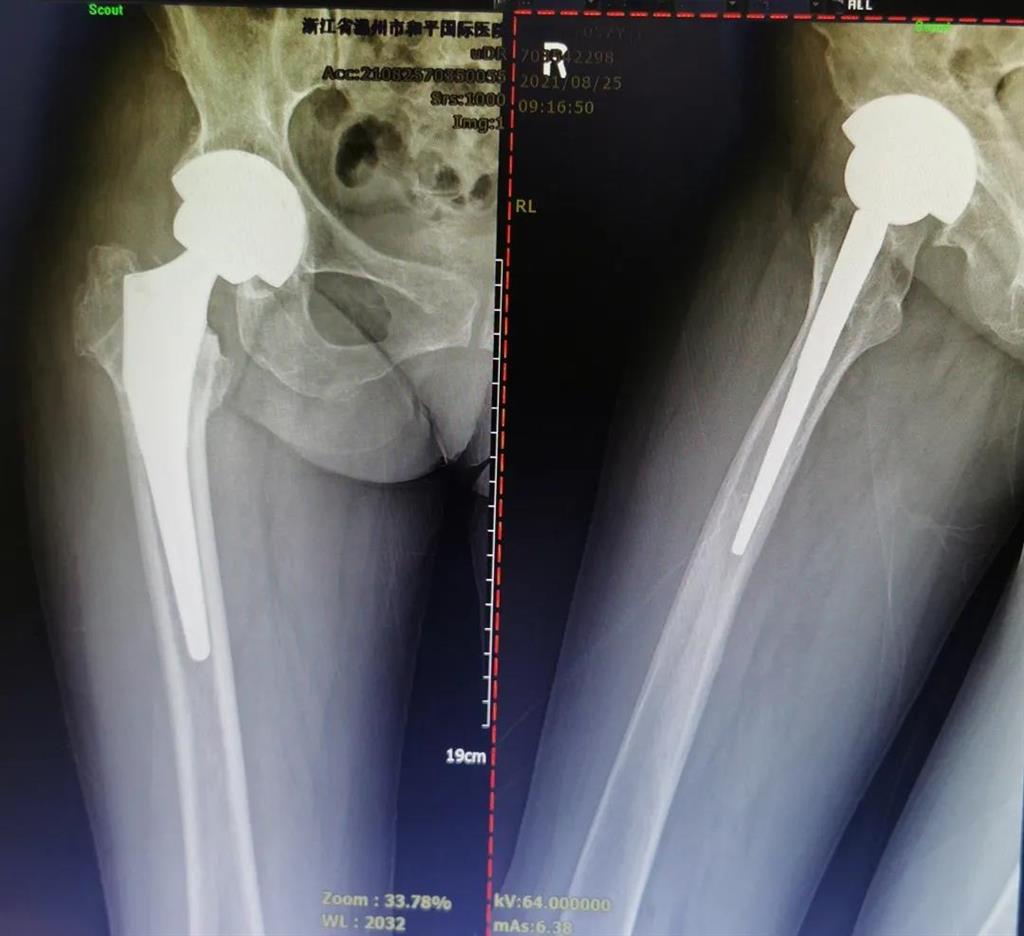

結合病癥表現及影像顯示,李女士被診斷為“右股骨頸骨折術后股骨頭壞死”,需要盡快做手術。

(△術前影像,右股骨頸骨折內固定術后股骨頭壞死)

(△做完“右股骨頸全髖關節(jié)置換術”后的影像)